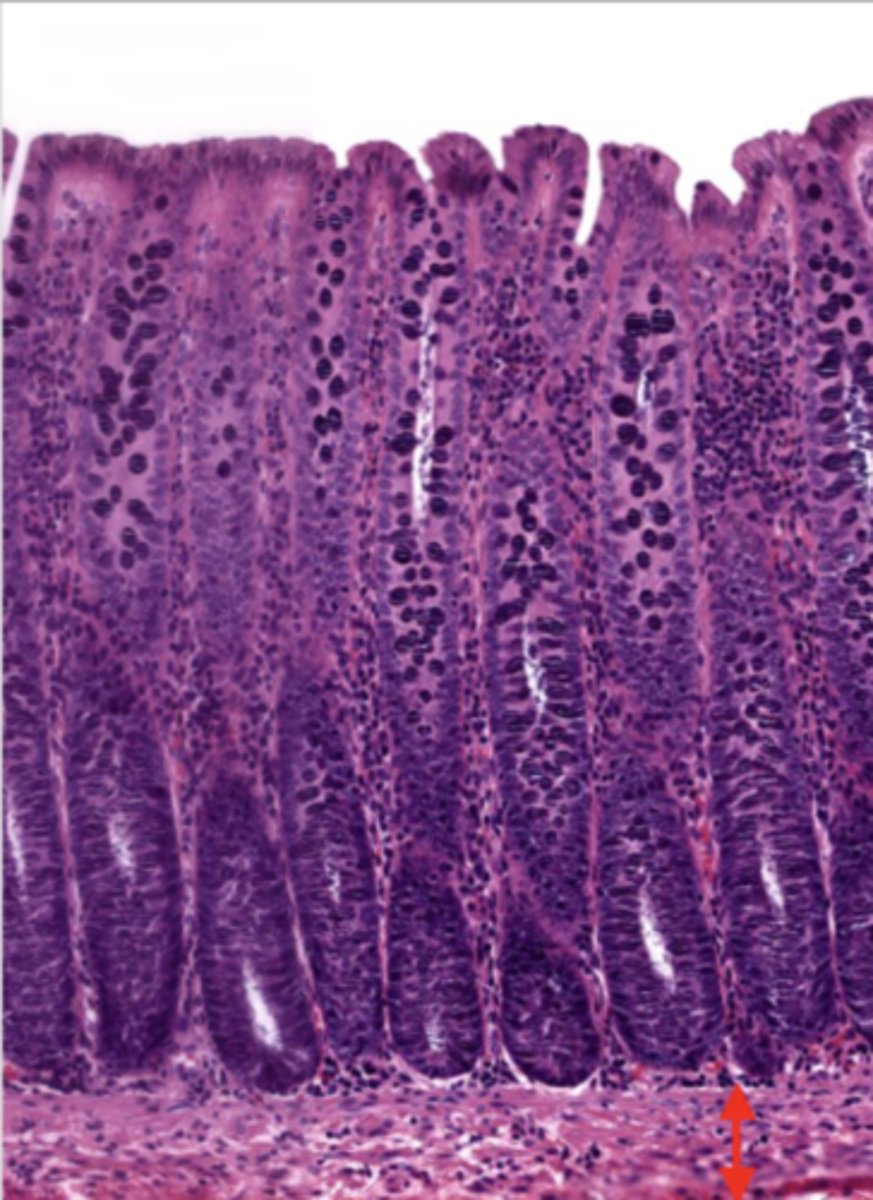

jejunum (histology)

simple columnar epithelium

what kind of epithelium lines the mucosa of the jejunum?

villi (jejunum)

intestinal crypts (jejunum)

lumen (jejunum)

mucosa (jejunum)

mucosal epithelium (jejunum)

lamina propria (jejunum)

muscularis mucosa (jejunum)

submucosa (jejunum)

contains glands and blood supply

muscularis externa (jejunum)

serosa/adventitia (jejunum)